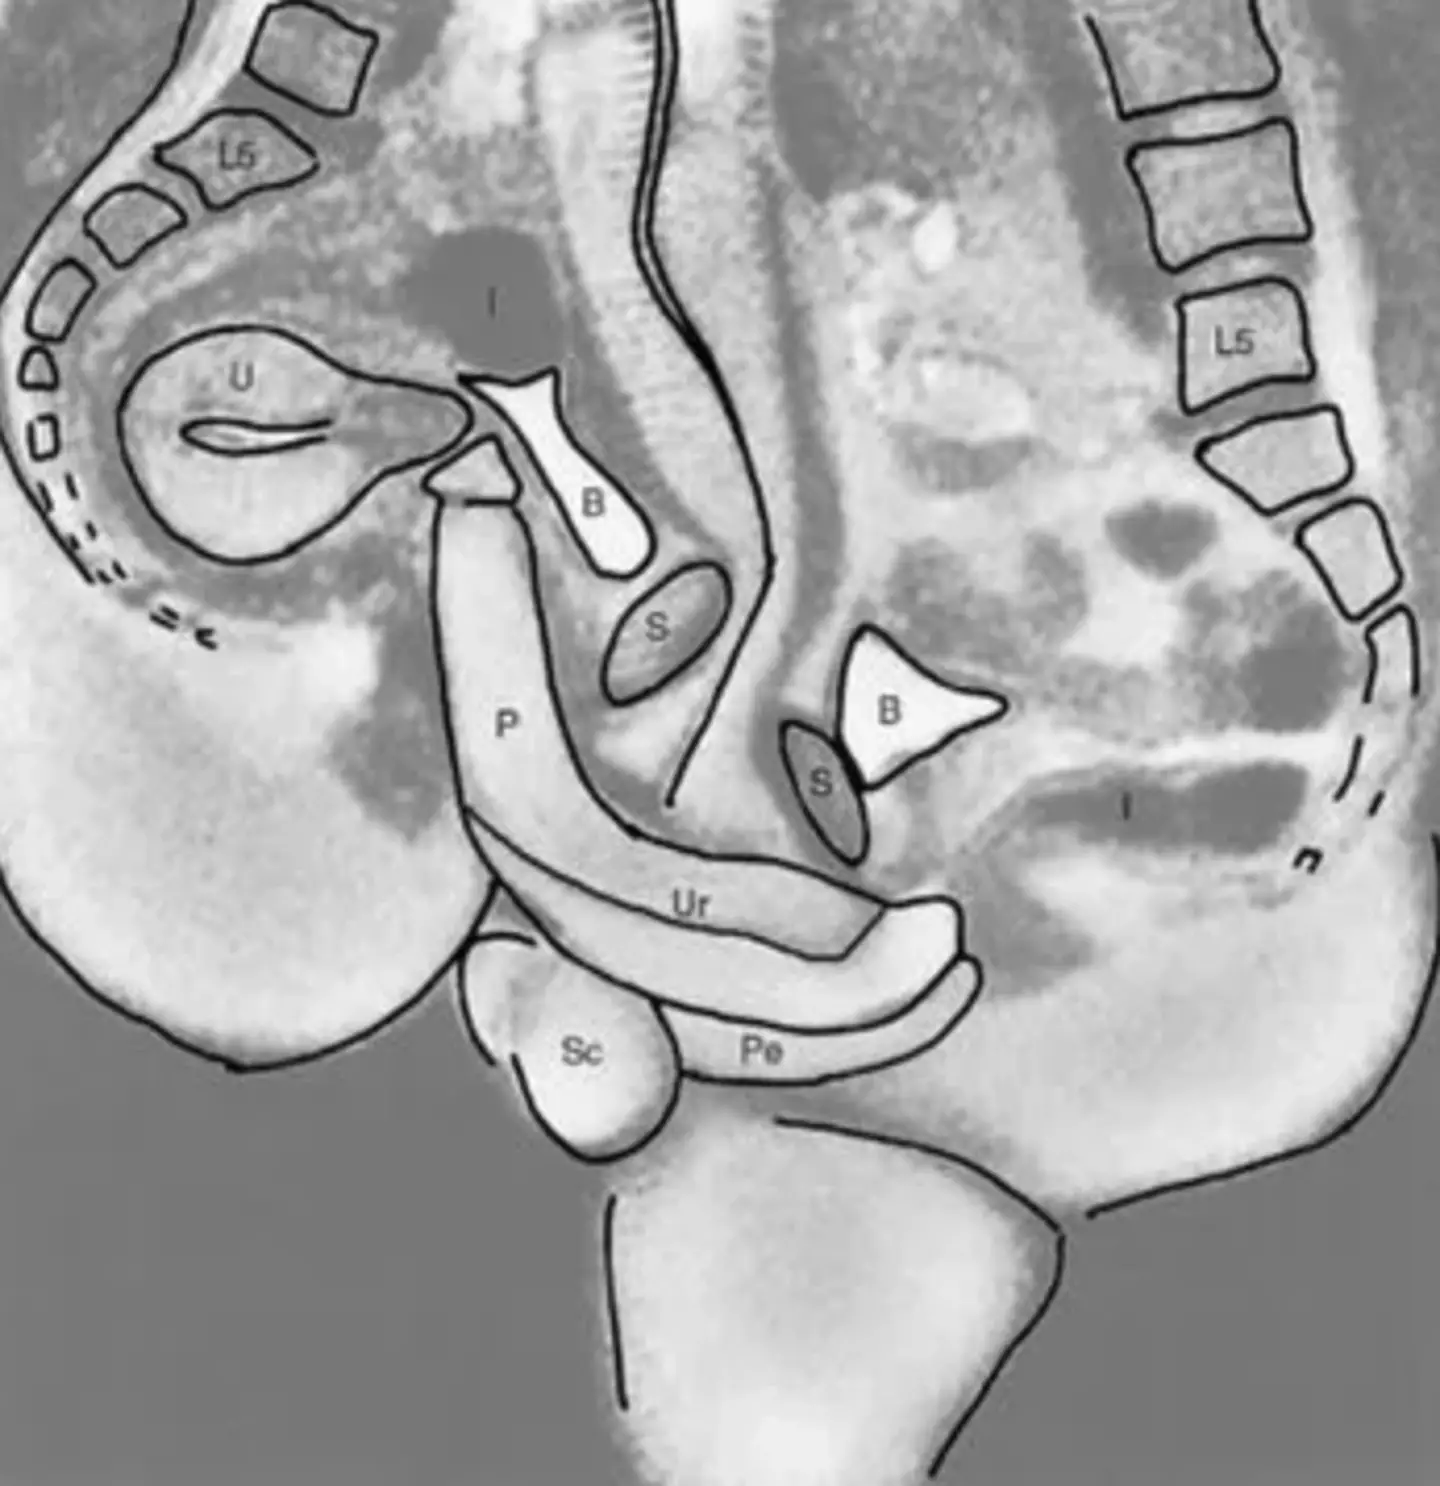

The images, if you want to see them, show two spines as well as genitalia and show exactly how the male and female bodies fit together during sex. If you wanted to study it more closely, there's even a handy key: P=penis, Ur=urethra, Pe=perineum, U=uterus, S=symphysis, B=bladder, I=intestine, L5=lumbar 5, Sc=scrotum.

The photographs, taken during the missionary position, were also useful scientific studies as they showed that the penis isn't straight during in sex but actually curved to fit the natural curve of the vagina.

Also, scientists had previously thought that the uterus expanded during sex but this was proven that despite female arousal, it doesn't appear to get any bigger.